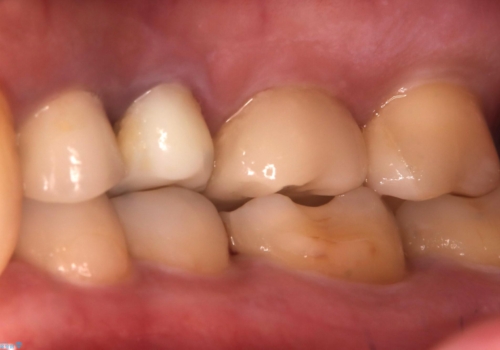

咬合力によるヒビの部分に生じる歪みを軽減するため、クラウンを被せました。

咬合力によるヒビの部分に生じる歪みを軽減するため、ヒビを追えるところまで切削しCR裏層・支台歯形成を行い、一度仮歯に置き換え症状の緩和を確認し、CAD/CAM冠を装着しました。